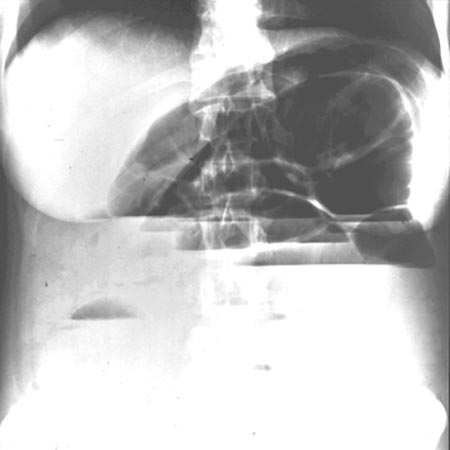

Konventionelles Röntgen des Bauchbereiches (Abdomendiagnostik)

Radiographie (Röntgenaufnahme) und Fluoroskopie (Durchleuchtung) sind die klassischen Röntgenverfahren zur Untersuchung des Darms. Neueste Technologien bei Strahlern, Detektoren (z.B. digitale Flachdetektoren) und in der computergestützten Bildnachbereitung kommen mit geringen Strahlendosen und kurzen Untersuchungszeiten aus. Nur das Kontrastmittel können wir Ihnen noch nicht ersparen.

Ileus